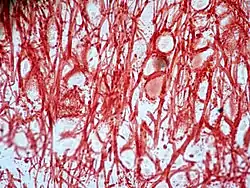

![]() Imagen tomada con microscopio óptico de cartílago elástico. | ||

El cartílago elástico es histológicamente similar al cartílago hialino, pero además de las fibras de colágeno tipo II del hialino, contiene muchas fibras elásticas. Estas fibras se ramifican y le dan gran flexibilidad al cartílago elástico,[1] de tal manera que es capaz de soportar flexión repetida. Se encuentra en la epiglotis (parte de la laringe) y el pabellón auricular (las aletas del oído externo de muchos mamíferos incluidos los humanos).[1] Las fibras de elastina se tiñen de púrpura oscuro / negro con la tinción de Verhoeff.